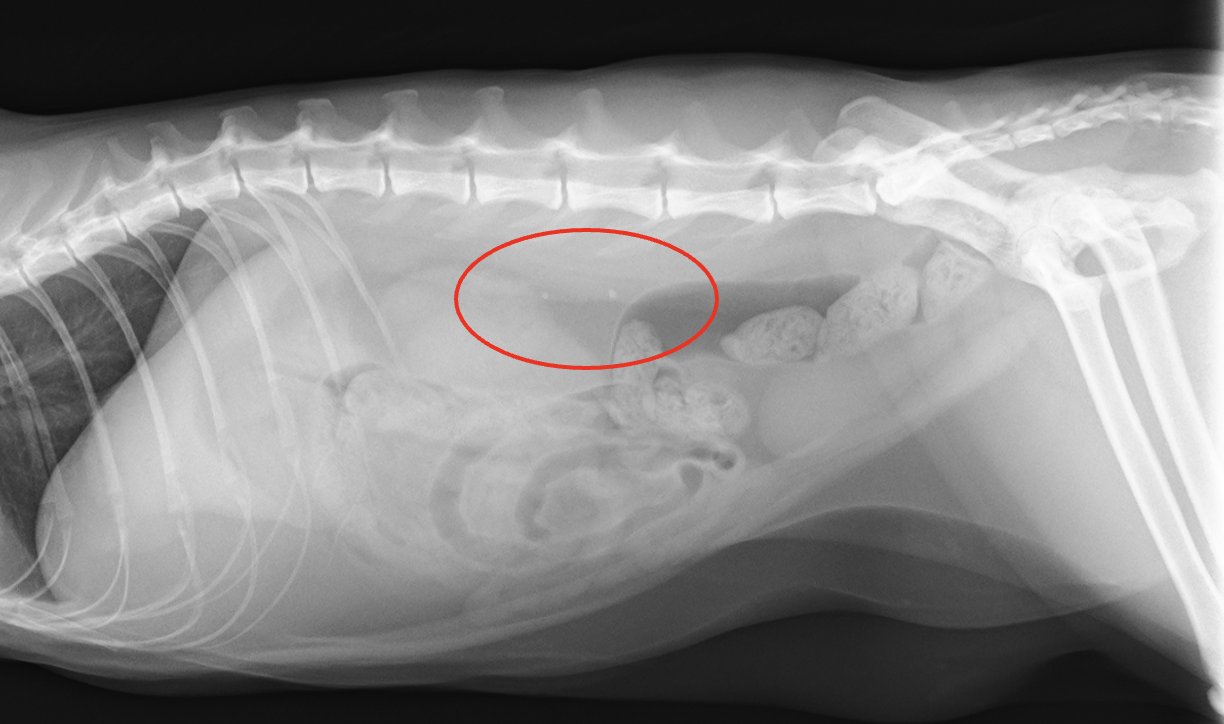

レントゲン、CT検査より左右の尿管に結石が認められた。また左腎臓腎盂の拡張が認められた。